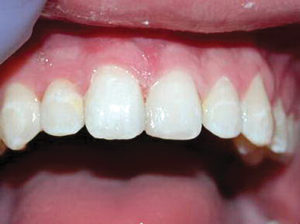

Un nuevo paciente de 7 años presentó una importante descomposición e hipocalcificación en el primer molar permanente superior derecho. Durante mucho tiempo se ha demostrado que los primeros molares permanentes cariados e hipocalcificados en pacientes pediátricos le dan al profesional un dilema restaurador difícil. ¿Deberíamos intentar prepararnos y restaurarlos conservadoramente? ¿Deberíamos ser más agresivos y restaurar con una cobertura completa como una corona de acero inoxidable bien adaptada? Activa proporciona una gran alternativa en estos casos, con liberación de calcio, fosfato y fluoruro junto con alta resistencia y resistencia a la fractura.

Figura 1. Después del ataque ácido y el uso del agente de unión Scotchbond Universal (3M), los dos molares primarios superiores se restauraron con Activa Bioactive Restorative A2. |

Figura 2. Una vez que se excavó la descomposición y se colocaron los márgenes en superficies sólidas, se colocó un bisel pesado en el esmalte para aumentar la resistencia de la unión y la integridad marginal. El área oscura central era sólida. El diente estaba revestido con una base / revestimiento Activa. |